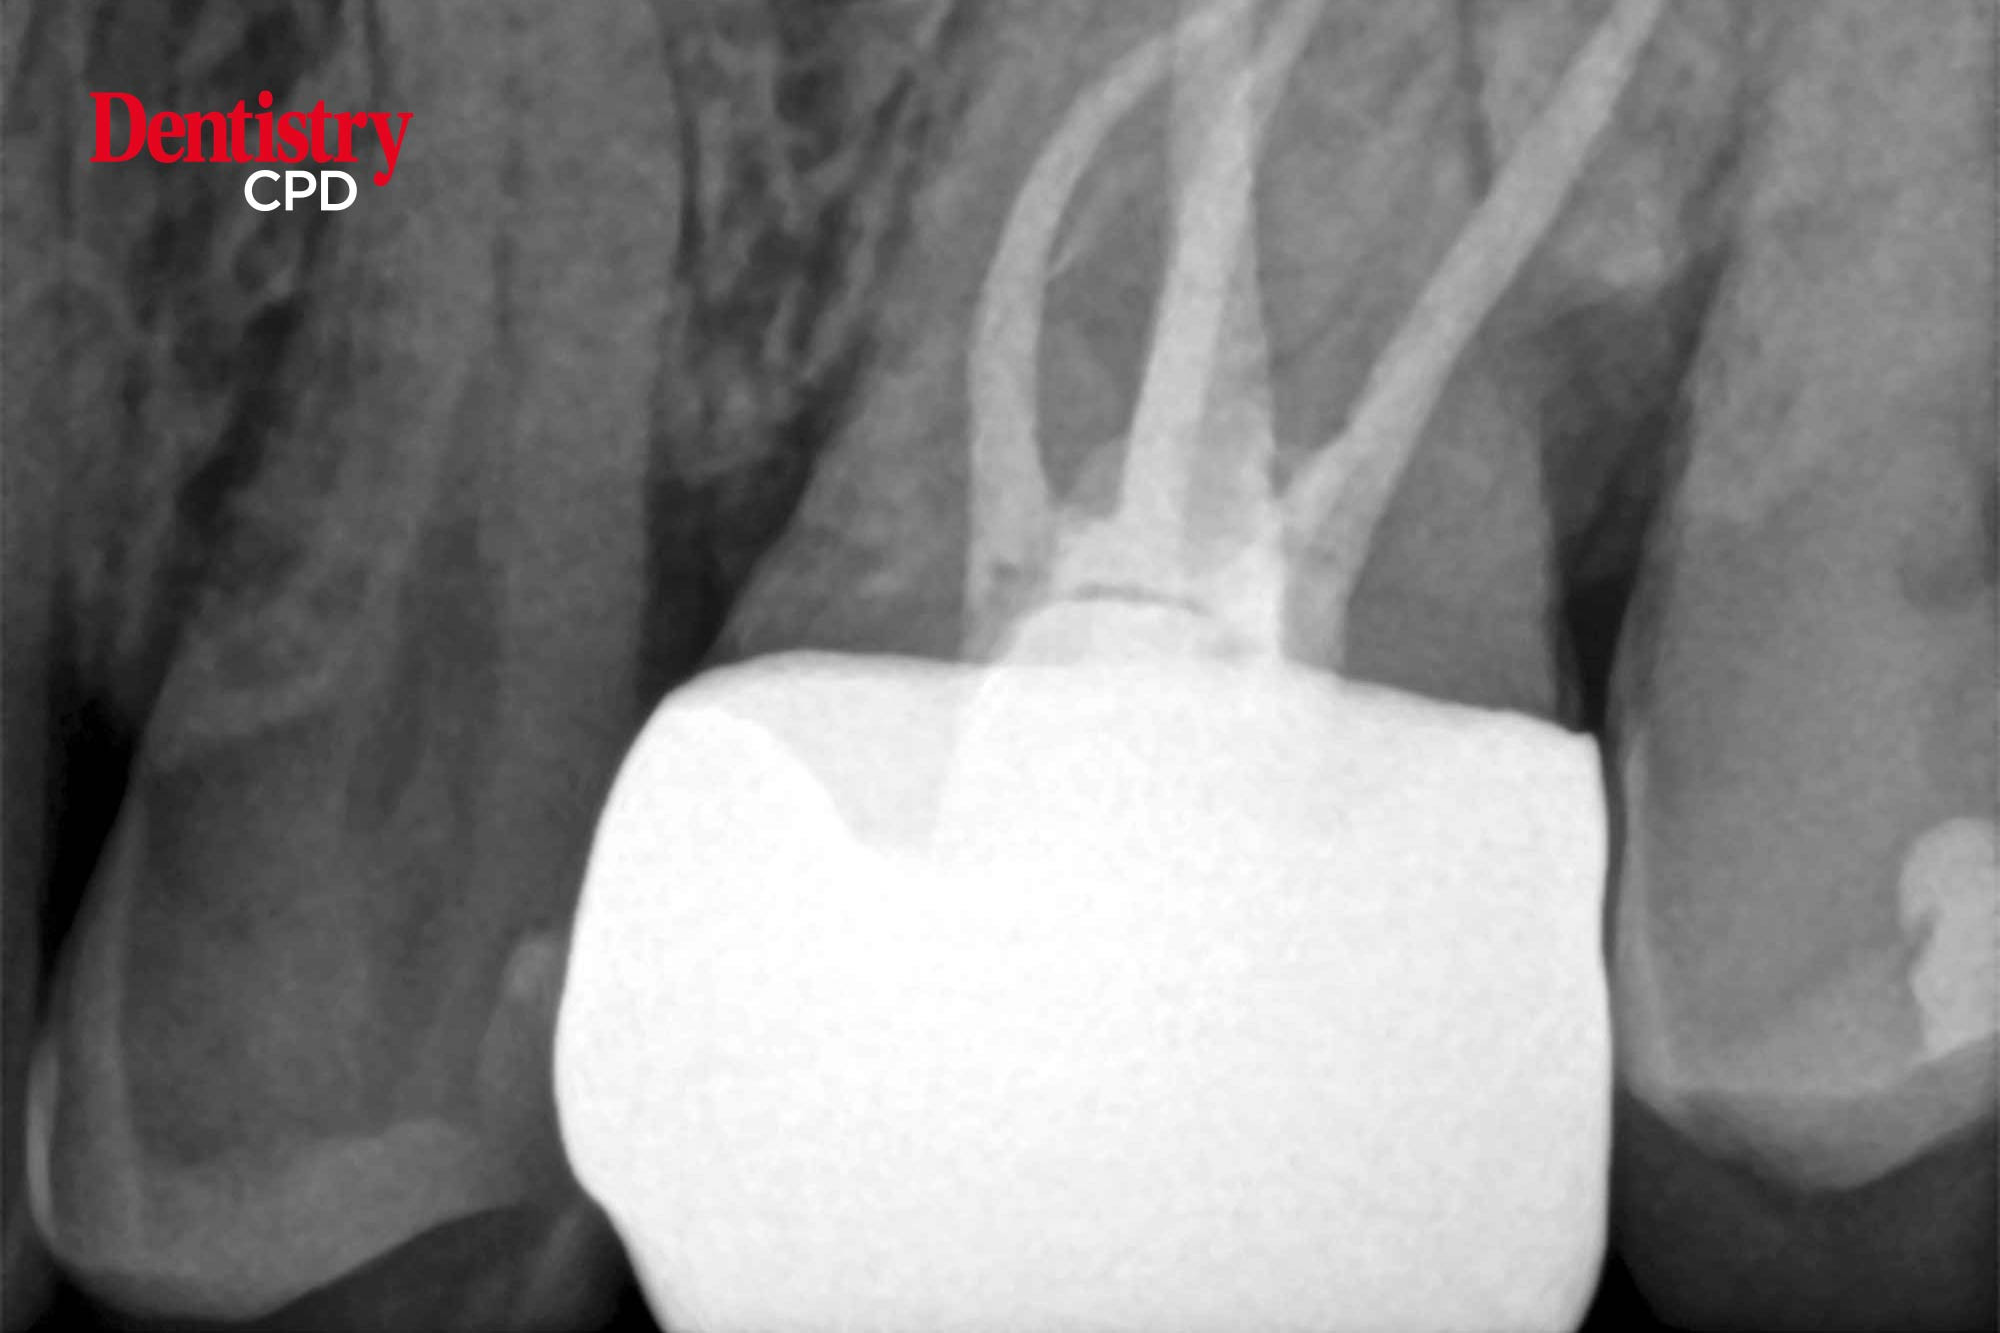

Minimally invasive, conventional and large root canal system endodontics: part two

Peet J van der Vyver and Martin Vorster present clinical applications of a new rotary file system.

To present clinical applications of a new rotary file system.